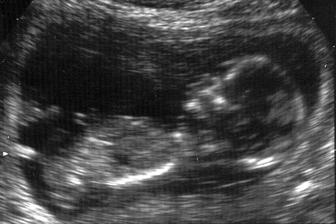

Pupíček se klube na svět

Snažit jsme se začali v září 2006, protože jsme chtěli spíše letní dítko. Hlavně aby nemělo narozeniny jako oboje rodiče v zimě... A protože člověk míní a život mění, jindy to snad ani vyjít nemohlo a čekáme dalšího Ježíška. Ve chvíli, kdy mě chtěl začít pan doktor léčit a předepsal mi prášky, rázem už nebyly potřeba. Ani jsem je nestačila začít brát. Pupíček by měl přijít na svět v půlce prosince, ale věřím, že když už se to takhle povedlo, vydrží s premiérou minimálně přesně na Vánoce 🙂